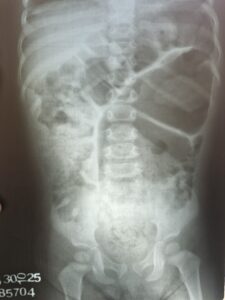

Durante o exame físico, a pediatra observa que o paciente está desnutrido e apresenta distensão abdominal importante, com desconforto à palpação e presença de fecaloma palpável. Ânus tópico. Ausência de náuseas ou vômitos. Ela solicita então uma radiografia de abdome.

Diante da história clínica e imagem, qual seria a principal hipótese diagnóstica?